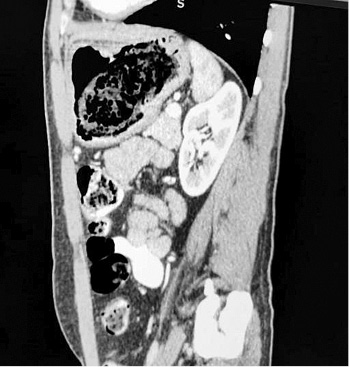

A thirty two years old male patient presented to our surgery department with complain of postprandial abdominal pain, early satiety and occasional vomiting episodes. He lost 5–6 kg in the past 6 months. The symptoms were present for the last 1 year. No comorbidity was reported. Previously he underwent a gastroscopy in another hospital where a stomach bezoar and large ulcer was diagnosed (Figure 1). Plain x-ray (Figure 2), computerized tomography (CT) scan (Figures 3 and 4) and gastroscopy were conducted in our institution. The gastroscopic examination reported giant rough bezoar impossible for endoscopic retrieval.

sagital-4.jpg

Figure 4. Sagittal computerized tomography scan